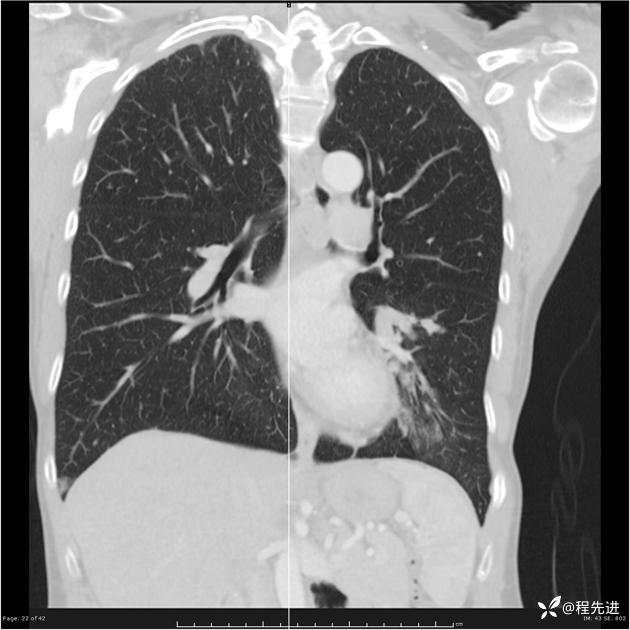

病例女,53岁,气管、左主支气管、下叶支气管内结节,乳头状瘤?期待你的精彩解读

女,53岁

乳头状瘤?